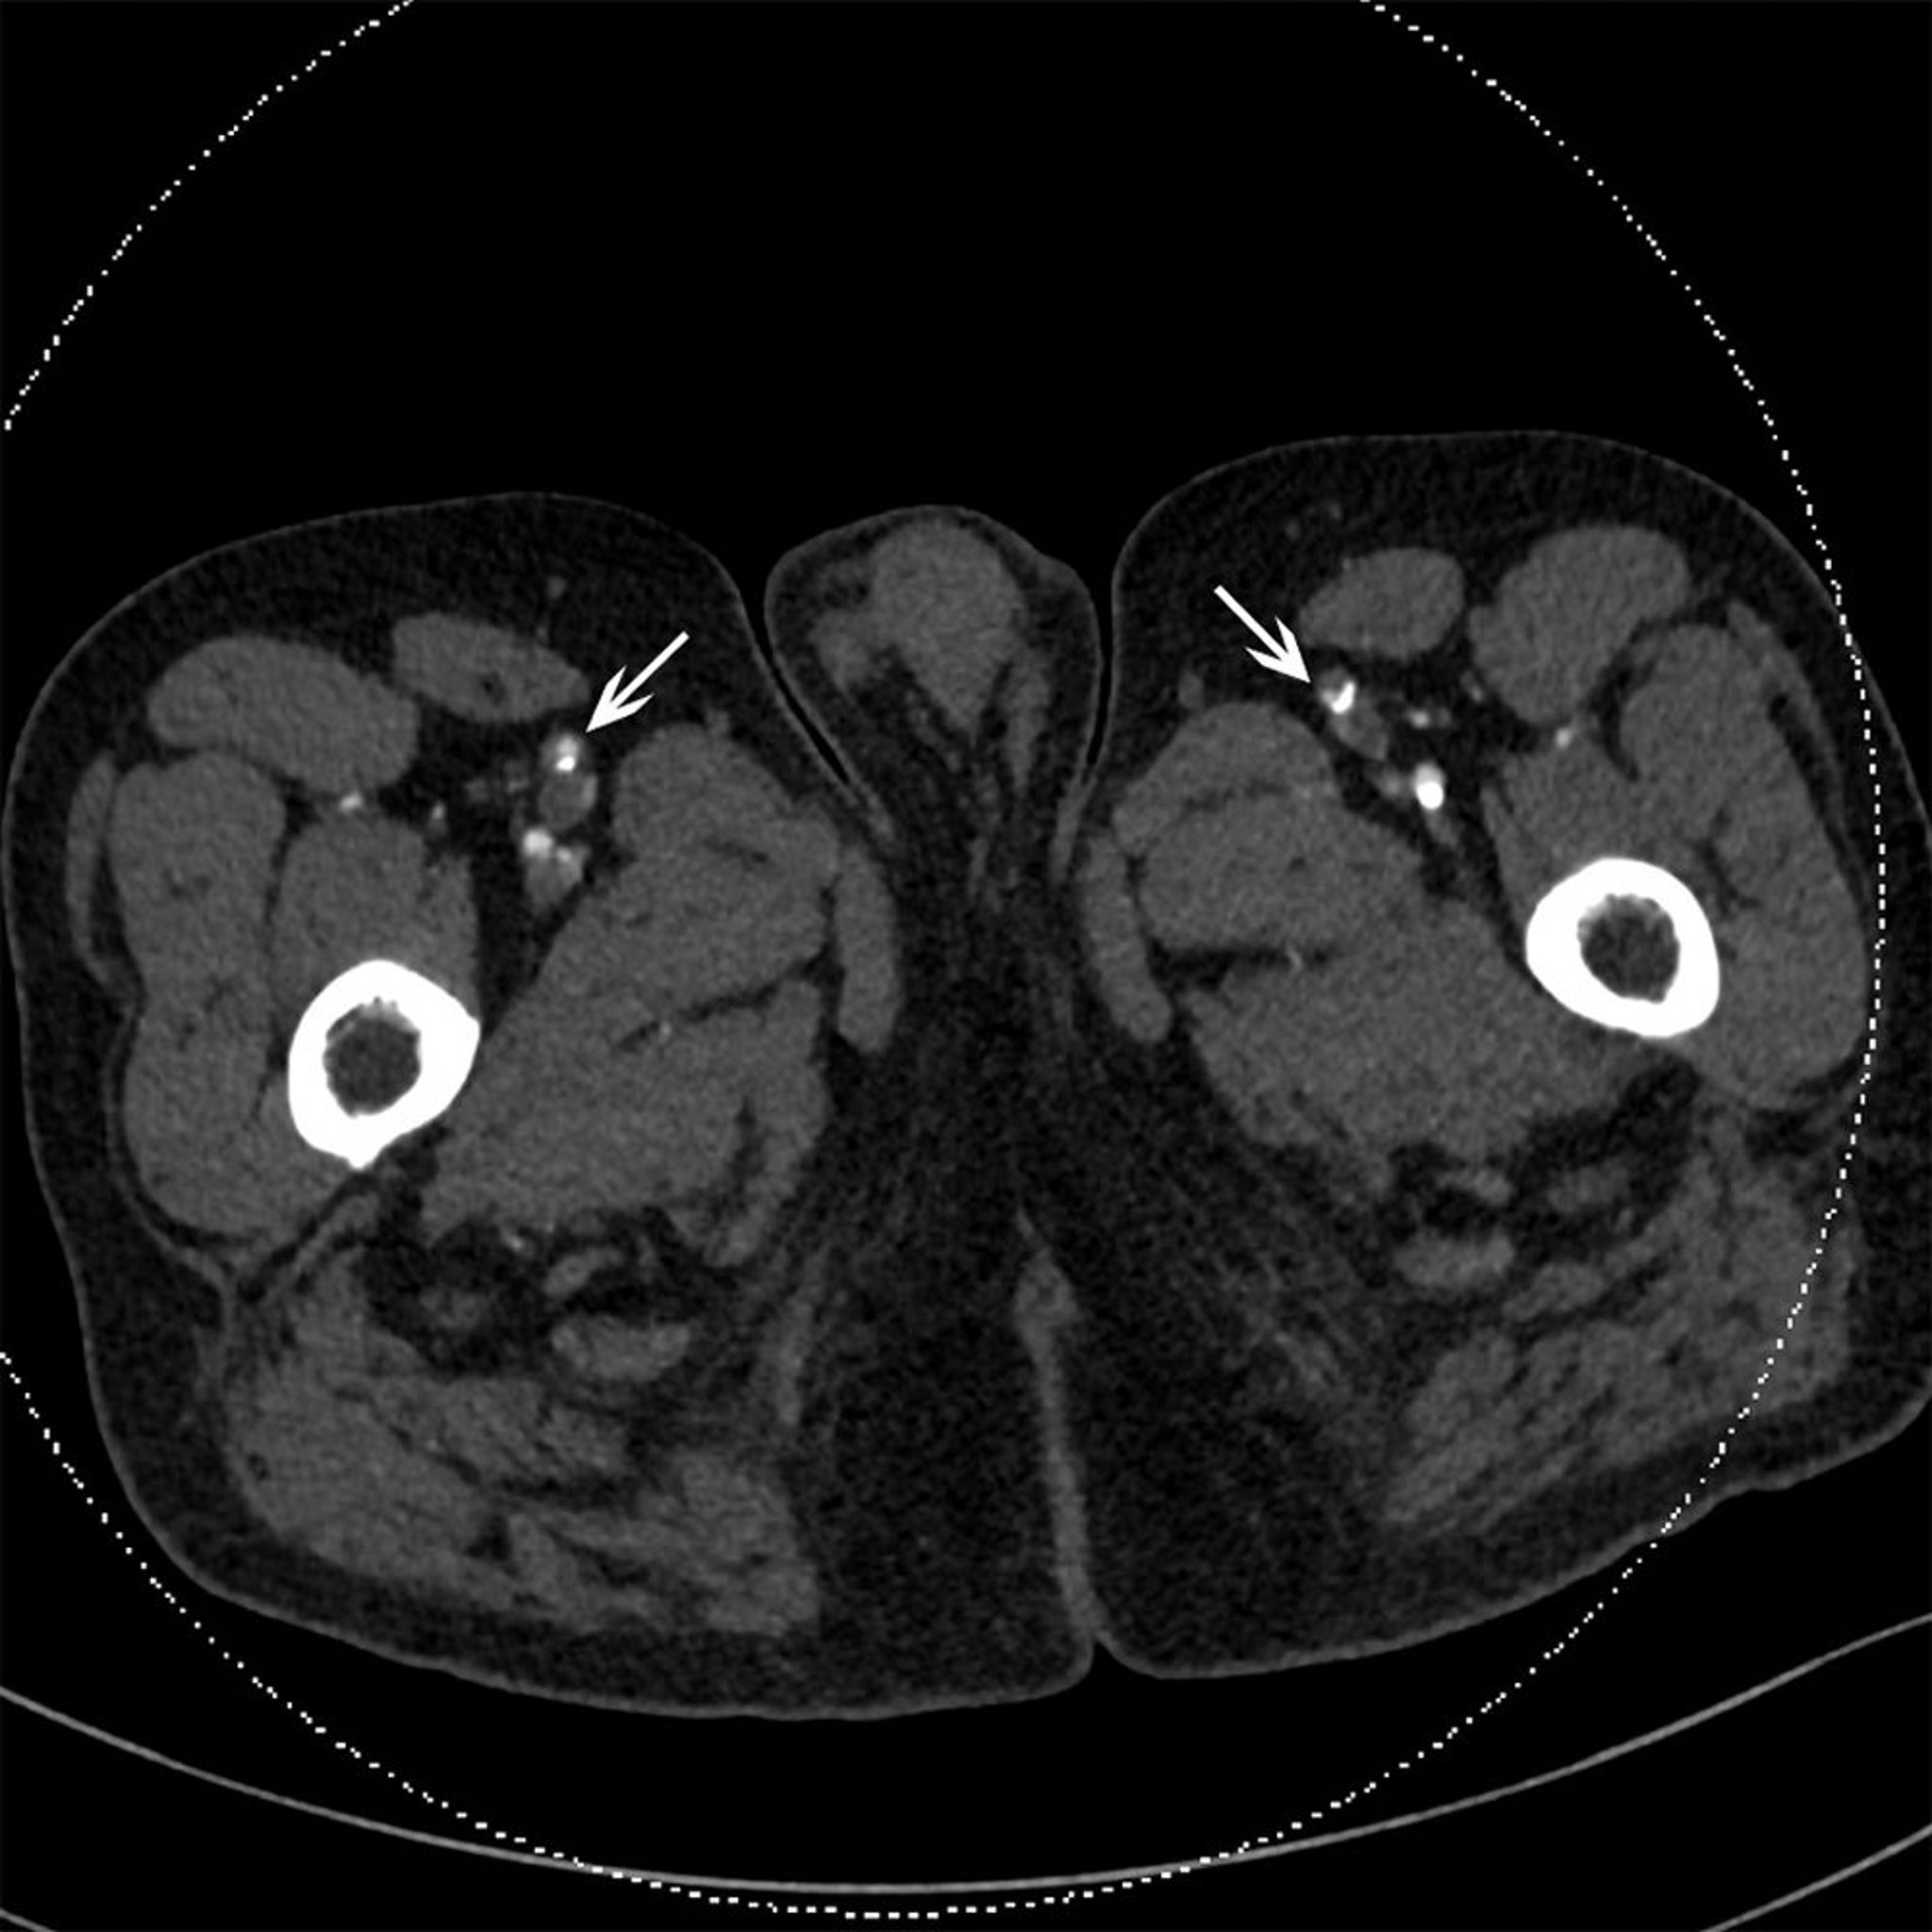

Tomografía computarizada de un paciente con oclusión de las arterias femorales superficiales

Esta TC muestra una placa calcificada bilateral en las arterias femorales superficiales (flechas).